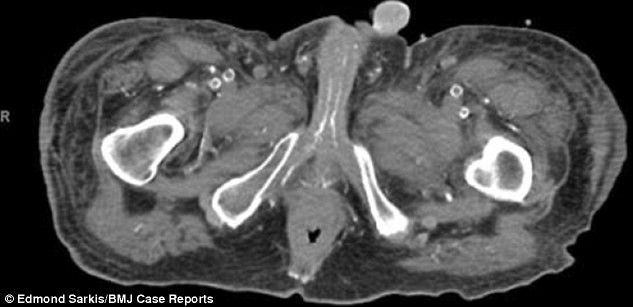

He cut off the upper part of the penis, because it had "died" as a result of blood poisoning

It had to amputate top part of the penis, because he started tarnished and not work as a result of blood poisoning.

54-year-old man was admitted to hospital with gangrenous wounds in the legs, buttocks, thighs and penis.

His wounds, which were black and the side parts were starting to drain, had made the unnamed man have very big pain.

BMJ Case Reports that he had to give strong sedative, in order to calm the situation as soon as his little, reports Telegraph.

Doctors at the hospital in New Yersey Cooper, have decided to amputate the penis, which they considered "dead".

"We saw during these wounds had begun to reek" said Dr. Edmond Sarkis, who was in charge of the team, who did the amputation. / Telegraph /